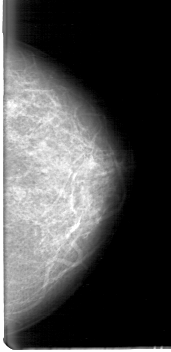

D_4067_1.LEFT_MLO

D_4067_1.LEFT_CC

LEFT_MLO LINES 5386 PIXELS_PER_LINE 3121 BITS_PER_PIXEL 12 RESOLUTION 43.5 NON_OVERLAY